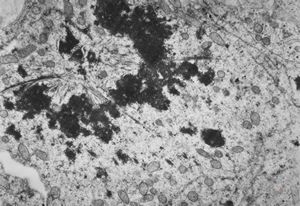

M,4y. | mitosis - retroperitoneal neuroblastoma